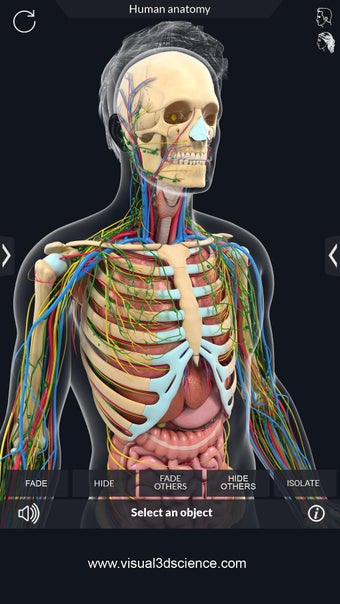

La anatomía humana es una aplicación educativa médica que te permite explorar el cuerpo humano desde todos los ángulos. Ofrece una mirada detallada a la anatomía de los diferentes sistemas, así como a los órganos y sus funciones. Es una referencia perfecta para estudiantes y profesores de medicina.

Puedes seleccionar cada parte del cuerpo por separado para ver su nombre o leer información relacionada. Puedes ocultar y mostrar cada parte del cuerpo, así como rotar 360° alrededor de un modelo 3D altamente realista. Puedes dibujar en la pantalla o compartir capturas de pantalla con tus amigos. Puedes encontrar la definición de cada parte del cuerpo y su anatomía.